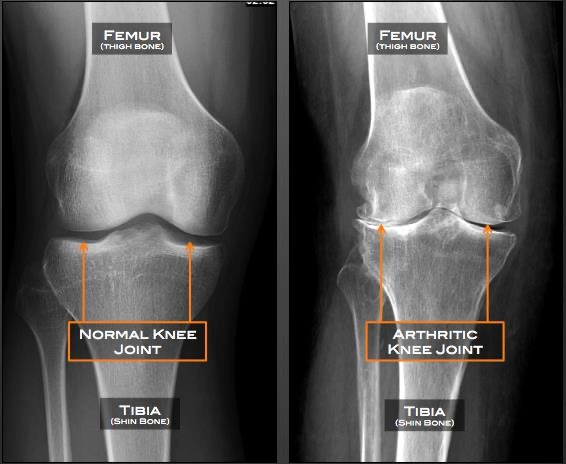

A reduction of joint space between the femur and tibia, which would indicate a loss of cartilage in the knee, can be seen on x-rays (see image below). In extreme cases, the two bones will be touching. Bone spurs (osteophytes) can also be seen on an x-ray.

Knee X-ray of a normal (left) and an osteoarthritic (right) knee. Note the reduction in space between the two bones.